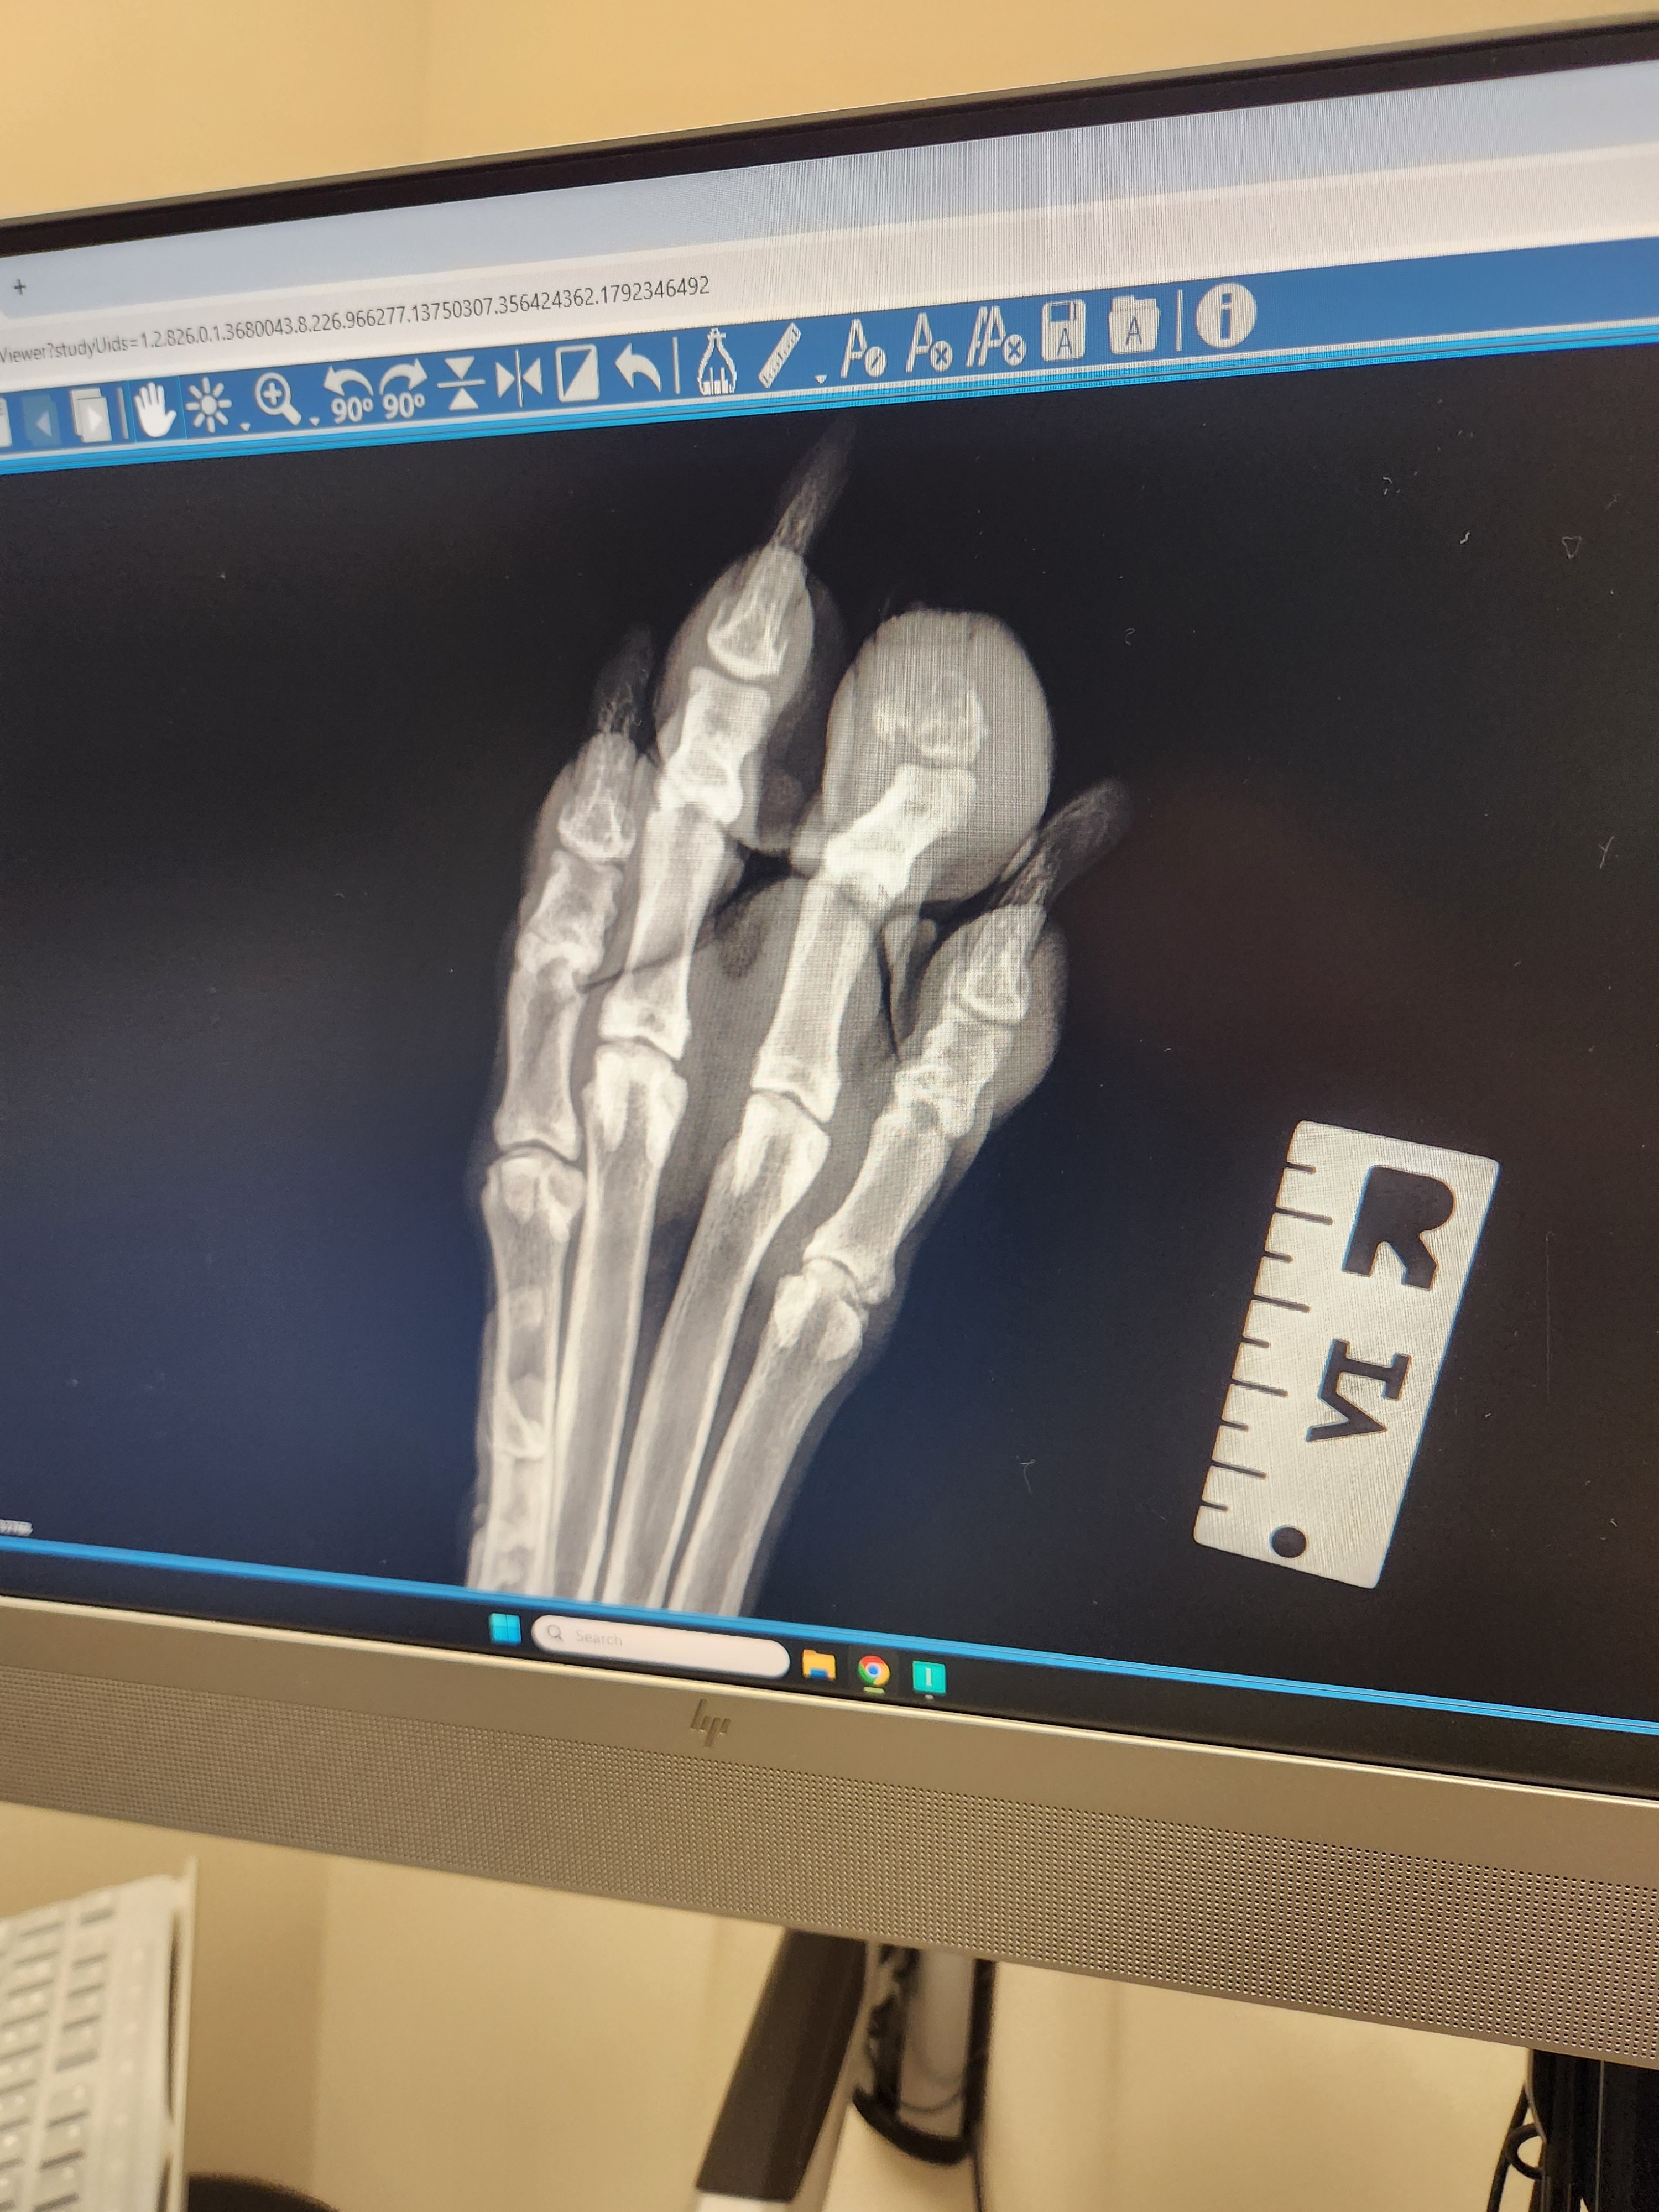

Well, it's been a couple of weeks now and he has started to develop some dry coughing and we noticed the toe seemed a bit more swollen. So, I called our vet and took him straight in on 5/23/25. They recommended X-rays to be done on the paw and lungs. Results came back that Diesel has air bronchograms in the lungs and cancer findings on Phalanx 3. We were told that with the findings from the X-ray, Diesel has to have a toe amputation. There are 2 types of bone cancers explained: Sarcoma, in which case the amputation would be curative, and Osteosarcoma, which is aggressive and would only give him 6 months to live, worst case scenario. The amputation is the only way to send it for a biopsy to determine what cancer it is. The vet told us the sooner the better. Being that Diesel is so loved, we already set the operation date for 5/30/25.